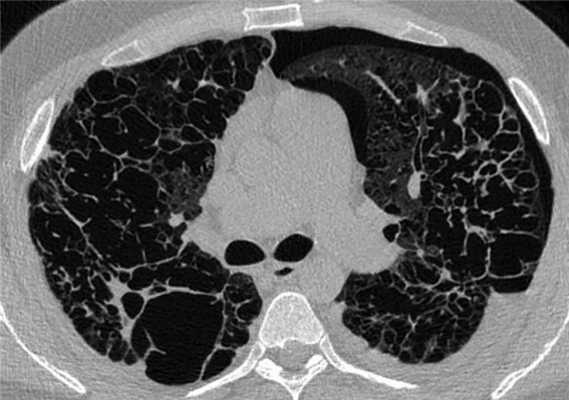

Рентгенологическая картина гистиоцитоза легких меняется в зависимости от стадии развития заболевания. Наиболее информативным рентгенологическим методом исследования при ЛКГЛ является компьютерная томография высокого разрешения (КТВР). На ранних стадиях заболевания при выполнении КТВР выявляют мелкие (3-6 мм, реже до 1 см) симметричные узелки в верхних и средних отделах легких, по мере прогрессирования заболевания появляются полости (рис. 1) Рисунок 1. КТ легких. Множественные симметричные узелки и полости в верхних отделах легких. , число которых со временем нарастает при одновременном регрессе узелков [7]. При длительном течении заболевания определяются множественные полости и участки «сотового легкого» (рис. 2) Рисунок 2. КТ легких. Множественные полости и участки «сотового легкого». . Для гистиоцитоза легких, в отличие от других интерстициальных заболеваний легких, патогномонично симметричное поражение верхних и средних отделов легких, поражение нижних отделов легких имеет место при тяжелом течении заболевания. Гистиоцитоз у взрослых чаще протекает в форме изолированного поражения легких, однако в 15% наблюдений имеет место поражение костей скелета, реже лимфатических узлов, кожи и других органов [8].

Пациент П., 36 лет с анамнезом курения 20 пачка/лет, в настоящее время отказался от курения в связи с тяжестью состояния. Предъявлял жалобы на одышку в покое, усиливающуюся при минимальной физической нагрузке, кашель с отделением светлой мокроты и редкие эпизоды кровохарканья. Впервые за медицинской помощью обратился в 2010 г., был диагностирован рецидивирующий правосторонний пневмоторакс (3 эпизода), выполнен плевродез. В дальнейшем пациент стал отмечать одышку, не купирующуюся бронходилататорами. В 2013 г. в течение 6 мес принимал кортикостероиды. В июне и июле 2013 г. перенес 3 эпизода левостороннего пневмоторакса. При КТВР в июле 2013 г. выявлены множественные воздушные полости во всех отделах легких (рис. 10) Рисунок 10. КТВР. Множественные тонкостенные полости, сливающиеся между собой, субплевральные участки интерстициального фиброза. , сливающиеся между собой, а также участки «сотового легкого», внутригрудные лимфатические узлы увеличены до 1,8 см. При рентгенологическом исследовании костей скелета литические очаги не выявлены. На ЭКГ выявлено резкое отклонение электрической оси сердца вправо и блокада задней ветви левой ножки пучка Гиса, что отражает перегрузку правых отделов сердца. При ЭхоКГ выявлена трикуспидальная регургитация 2-й степени с градиентом давления 50 мм рт.ст. и дилатация правых отделов сердца как подтверждение вторичной легочной артериальной гипертензии. При исследовании функции внешнего дыхания ЖЕЛ =2,39 л (46,1%), ОФВ 1 =1,30 л (30,4%), ОФВ 1 /ЖЕЛ =54,51%, DLCO =10,40 (29,6%), что отражает выраженное нарушение вентиляции легких по обструктивному типу. В связи с тяжестью состояния в сентябре пациент был включен в лист ожидания трансплантации легких в НИИ СП им. Н.В. Склифосовского, в октябре выполнена успешная двусторонняя пересадка легких. В настоящее время состояние пациента удовлетворительное.